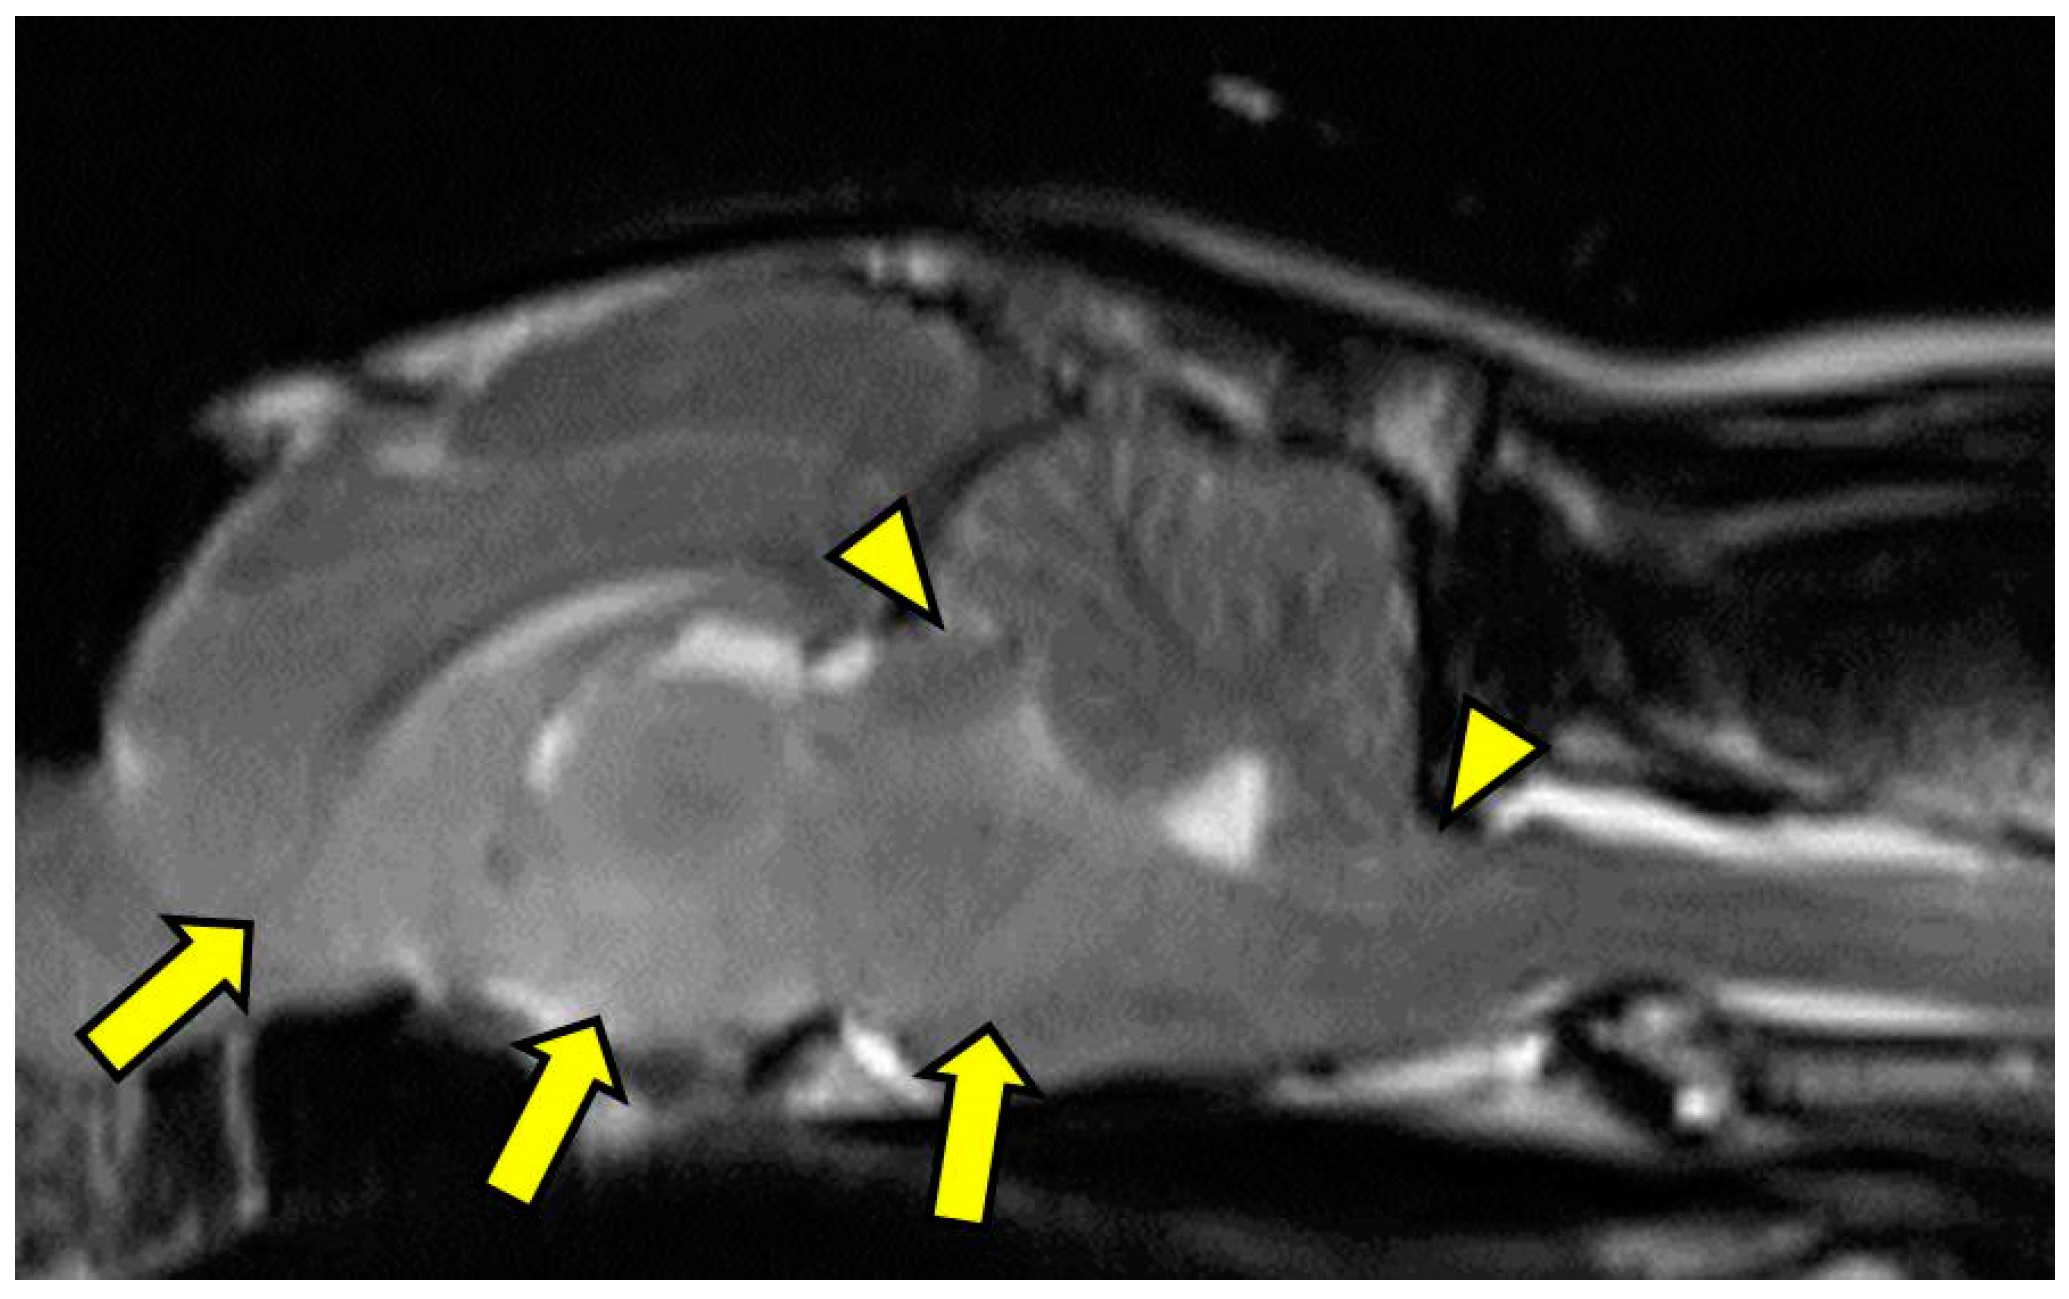

On MRI scanning of the brain, an intra-axial, diffuse, non-contrast-enhancing, T2-weighted, hyperintense mass effect extending through the ventral forebrain (including the piriform and temporal lobes, thalamus, crus cerebri, and colliculi) and midbrain (Figure 1) was found. The caudal aspects of the cerebellum were compressed against the occipital bone. There was also caudal transtentorial herniation of the midbrain and herniation of the cerebellar vermis through the foramen magnum (Figure 2). A linear, T2 hyperintense area was present in the dorsal aspect of the C2-C5 spinal cord; transverse images of this area showed dilation of the central canal, T2 hyperintensity, and non-contrast-enhancing T1 hypointensity in the dorsal spinal cord, most consistent with syrinx formation. Based on clinical findings and MRI results, differential diagnoses included multicentric neoplasia or an infectious etiology such as feline infectious peritonitis (FIP), feline immunodeficiency virus (FIV), feline leukemia virus (FeLV), or cryptococcosis. Due to poor prognosis and rapid clinical decline, the cat was humanely euthanized.

Figure 2. T2-weighted midline sagittal image showing caudal transtentorial herniation of the midbrain through the osseous tentorium and caudal herniation of the cerebellum through the foramen magnum (arrowheads). Additionally, there is an ill-defined, mildly hyperintense mass effect in the ventral aspect of forebrain including the caudal nucleus of the thalamus, interthalamic adhesion, colliculi, and midbrain (arrows). MRI scan.